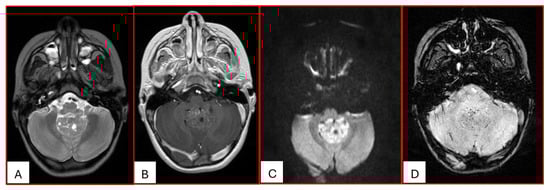

On computed tomography (CT), AT/RTs typically appear hyperdense owing to their high cellularity, and calcifications are frequently identified. Magnetic resonance imaging (MRI) findings are variable on both T1- and T2-weighted sequences; however, restricted diffusion is usually present. Cystic or necrotic components, as well as intratumoral hemorrhage, are common features [15]. Arslanoglu et al. described the presence of eccentrically positioned cysts with peripheral wall enhancement as a potentially distinguishing characteristic of infratentorial AT/RTs (Figure 1). The pattern and degree of contrast enhancement are variable, further reflecting the histopathologic heterogeneity of these neoplasms (Figure 2 and Figure 3). A characteristic pattern of band-like enhancement surrounding a central cystic or necrotic area was observed in 38% of MRIs from a series of 32 patients [16].

Figure 3. Three-year-old female with ATRT. (A) Axial T2-weighted image shows a mass centered in the midline posterior fossa of heterogeneous intermediate signal with small cystic/necrotic changes. There is no surrounding edema. (B) This mass demonstrates mild heterogeneous enhancement. (C) There is prominent corresponding restricted diffusion. (D) A few foci of susceptibility are noted, which may reflect internal hemorrhage or calcifications. Note that the MRI features of this mass mimic the appearance of Medulloblastoma.